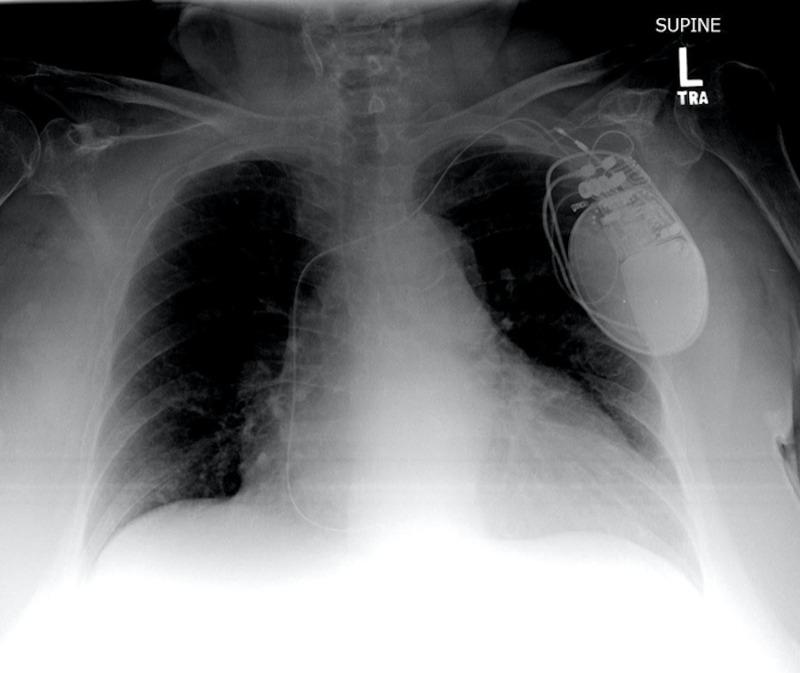

Automated Implantable Cardioverter Defibrillator/Pacemaker Lead Fracture.

Implanted artificial pacemakers are groundbreaking pieces of technology that have a vast array of medical benefits. However, as with other electronic devices, these implanted cardiac devices are not immune to failure. One of the most common failures are lead fractures, which can lead to conduction issues that result in inappropriate or insufficient electrical stimulation to the myocardium or other myocytes. The authors present a classic example of this type of artificial pacemaker failure, with the hospital course of a female patient presenting with erratic muscle contractions due to improper electrical impulse generation and conduction.